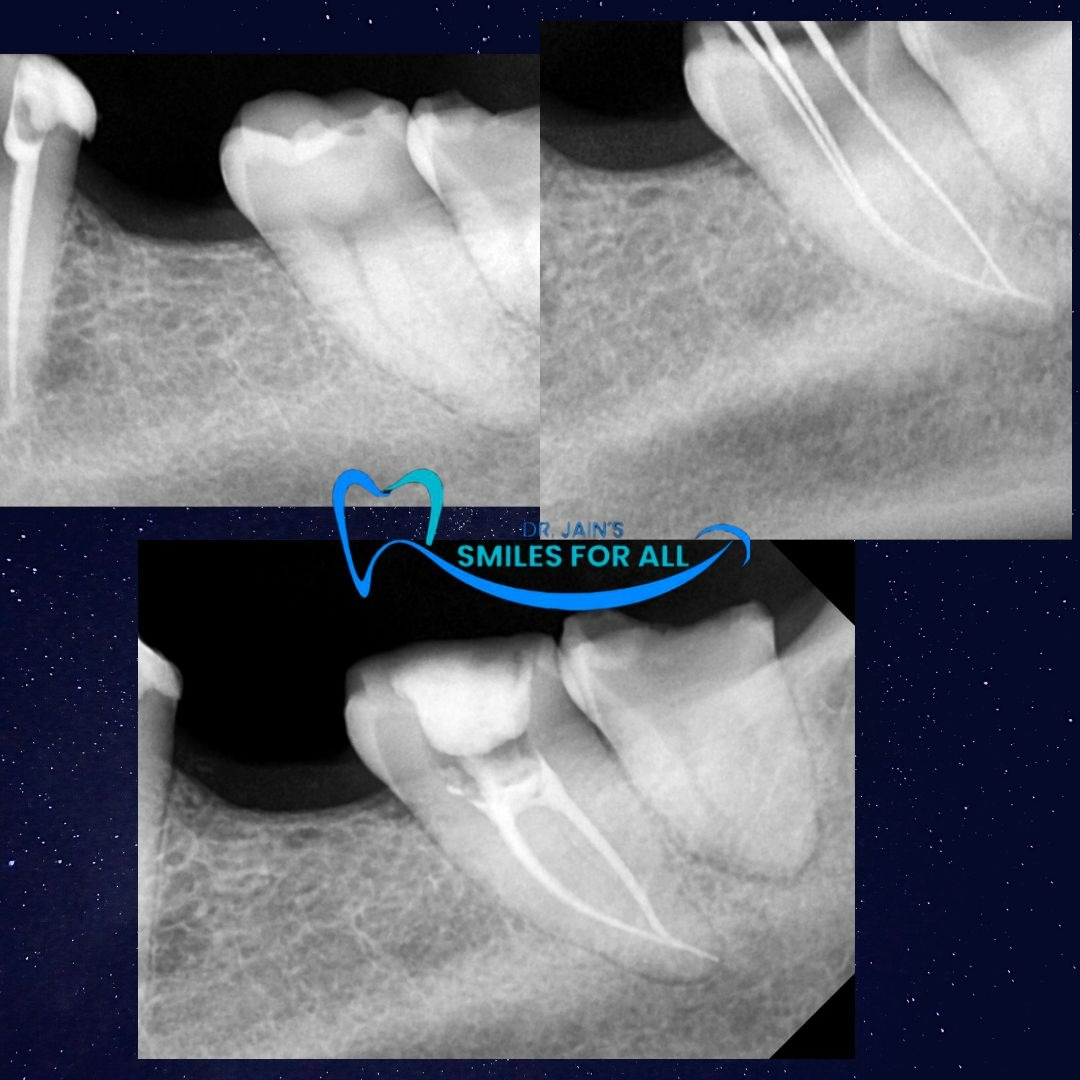

If you are struggling with constant tooth pain, sensitivity to hot and cold, or swelling near your gums, you may need a root canal treatment (RCT). At Smiles for All Dental Clinic, Rohini, we specialize in painless root canal treatments that save your natural teeth and restore your smile. Why Choose Root Canal Treatment? A root canal is needed when the inner part of the tooth (pulp) gets infected or damaged due to deep cavities, cracks, or trauma. Instead of removing the tooth, RCT helps: Eliminate pain and infection Save your natural tooth Prevent further dental complications Restore chewing and comfort Why Smiles for All Dental Clinic? Our clinic is recognized as one of the best dental clinics in Rohini for root canal treatment. Patients trust us because: Experienced RCT specialists with advanced training Use of latest technology for precise and comfortable treatment Options for single-sitting root canals in suitable cases A caring team that ensures a stress-free dental experience Beyond Root Canals Smiles for All is a multispeciality dental clinic in Rohini, offering comprehensive care such as: Dental crowns and bridges Dental implants Kids dentistry Preventive and cosmetic treatments Braces and Aligners Dentures Book Your Consultation Don’t let tooth pain take away your peace. Visit Smiles for All Dental Clinic, Rohini, and let our team of the best dentists in Rohini bring back your healthy smile. 📞 Call us today or book your appointment online!